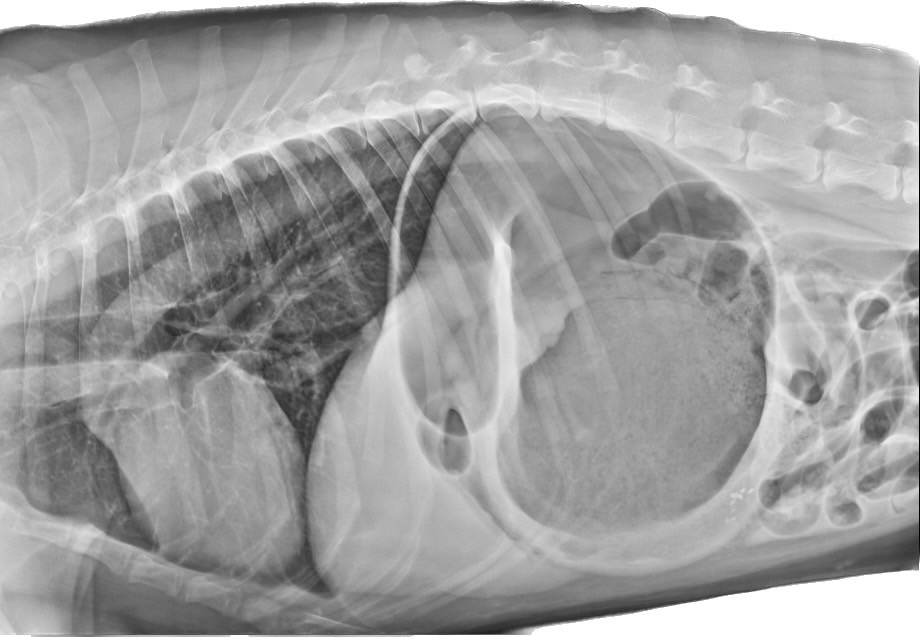

看到如此的症狀,答案也呼之欲出了,在X光下,小巴的胃非常擴張,且幽門部往前背側、左側位移,診斷為“胃擴張扭轉“

圖為腹腔X光